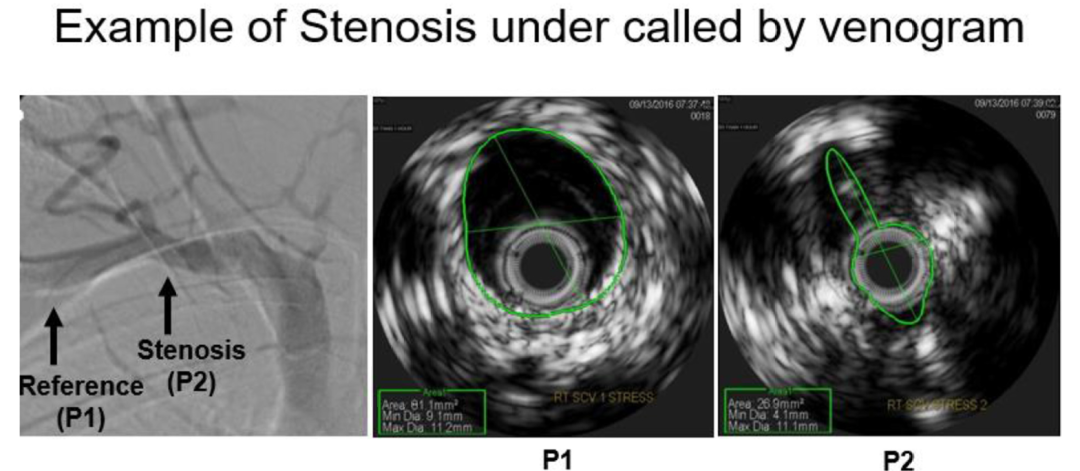

图示使用血管内超声(IVUS)测量值计算百分比狭窄的方法。本示例为横截面积(CSA)百分比狭窄的计算。以IVUS在点1(P1)处测得的CSA作为分母,以IVUS在点2(P2)处测得的CSA作为分子。通过将P2/P1比值乘以100,计算得到CSA百分比狭窄。类似的方法也用于计算头尾向及前后向的百分比狭窄,采用IVUS测得的CC和AP直径进行计算。

一例患者静脉造影与血管内超声图像的比较,该患者经血管内超声发现显著狭窄,但静脉造影未能显示。P1指第一肋骨外侧缘的参考点。P2指最狭窄点。